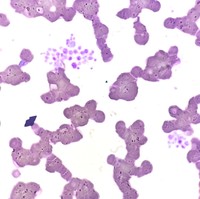

WBC Clumping

Peripheral blood smear of a patient with scrub typhus (IgM+) showing white blood cell clumping.